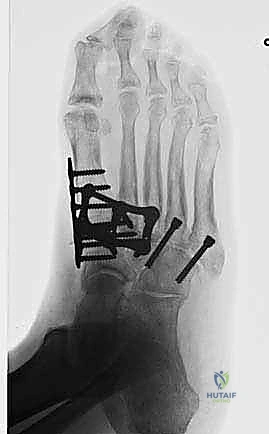

6. التثبيت الصلب (Rigid Fixation)

لضمان التحام العظام لتصبح عظمة واحدة صلبة، يجب تثبيتها بقوة هائلة حتى لا تتحرك أثناء فترة الشفاء. يتم استخدام مسامير معدنية متطورة (Screws)، أو شرائح معدنية خاصة (Plates)، أو دبابيس طبية متخصصة (Staples) مصنوعة من التيتانيوم الآمن على الجسم.

7. الإغلاق والضماد

بعد التأكد التام من وضع العظام وثباتها باستخدام جهاز الأشعة السينية داخل غرفة العمليات (C-Arm)، يتم إغلاق الشقوق الج